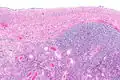

| Ovarian serous cystadenoma. The cystic space is at the top of the image. Ovarian parenchyma is seen at the bottom right. H&E stain. | |

Serous cystadenomas are diagnosed by histomorphologic examination, by pathologists. Grossly, they are, usually, small unilocular cysts that contain clear, straw-coloured fluid. However, they may sometimes be multilocular. Microscopically, the cyst lining consists of a simple epithelium, whose cells may be either:[3]

- be columnar and tall and contain cilia, resembling normal tubal epithelium

- be cuboidal and have no cilia, resembling ovarian surface epithelium